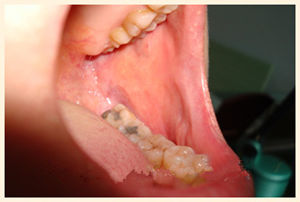

(朱先生治疗前的口腔内壁状态)